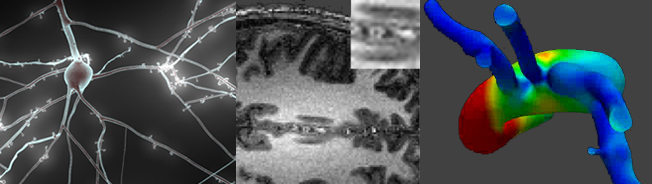

A major challenge in the biomedical field is the quantification of the complex behavior of biological systems. Computational techniques have an important role to play in the application of engineering principles to medicine and biology, leading to improved healthcare diagnostics and therapy.

EPFL contributes research in a number of different areas of biomedical engineering. The Blue Brain project aims to develop the capacity to construct a virtual brain, which will be an invaluable tool for neuroscientists in their understanding of the brain and neurological diseases. Simulation of the atomistic structure of complex biological systems can lead to fundamental understanding of the functional mechanisms of natural and clinical drugs. Numerical flow analysis of the arterial network of the human body can provide detailed insights into the origin of certain anomalies. Much of these research activities is undertaken in close collaboration with medical institutions, such as the CHUV.